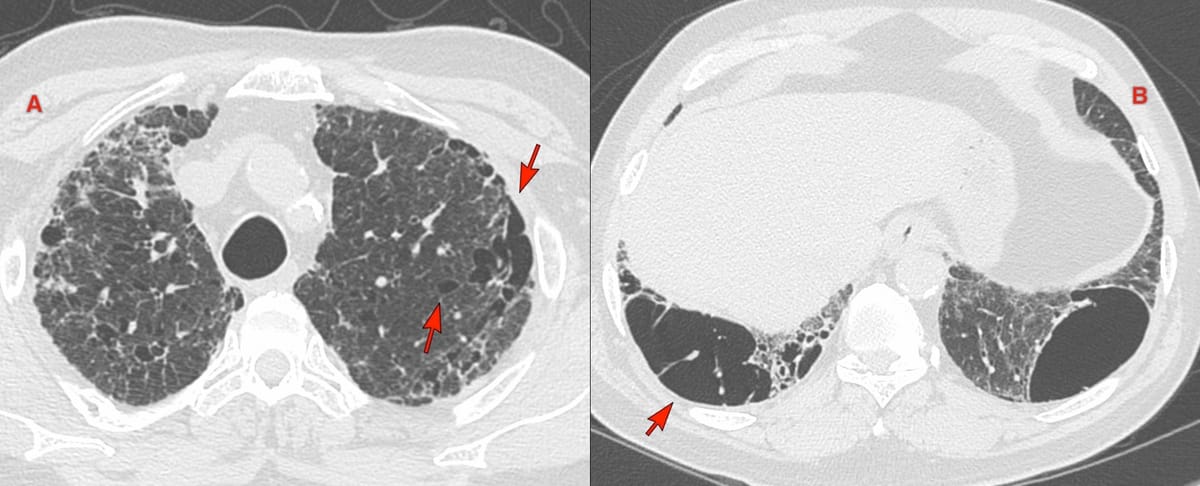

56-years old with an incidentally detected lung nodule in the superior segment of the right lower lobe of the lung. It showed one calcific speck. No contrast. No PET. There was extrapleural fat retraction, suggesting this could be extra-pulmonary.

On biopsy, it was firm. Histopath shows cartilage.

This is a peripheral chondroid hamartoma of the lung. Likely so longstanding, that the pleura has puckered around it.